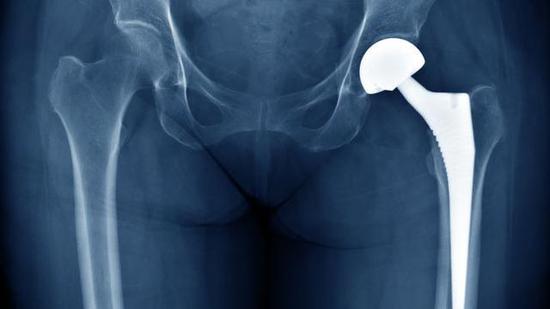

随着膝关节置换手术的普及,患者年龄呈降低的趋势,每年手术人数不断增加。其中很多人由于旧的植入体磨损或损坏需要再...

科学家发明以钛金属和黄金做成的新合金,可为现在的义肢设计带来革命。

Sciences Advances期刊,刊登了美国...